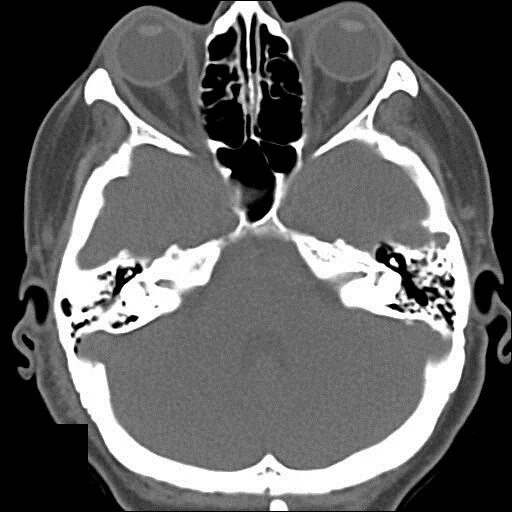

Череп на кт